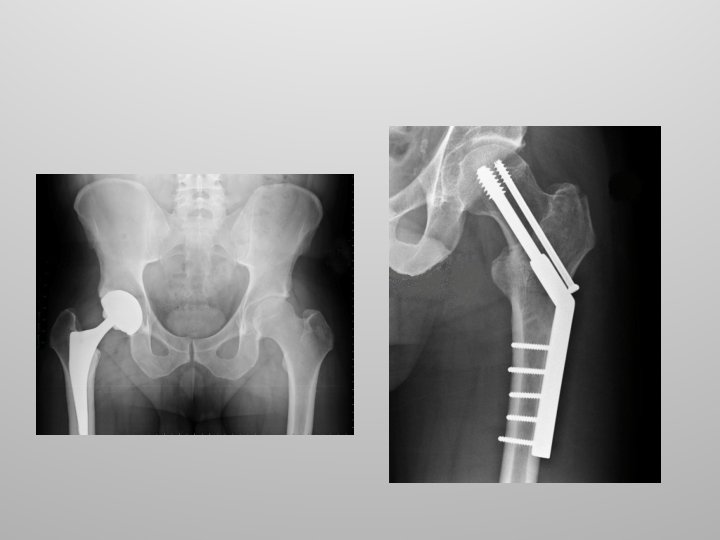

Hip Injuries Common injuries to the hip joint include fractures and dislocations. Hip fractures typically involve the neck of the femur and are the result of underlying disease such as osteoporosis.

Hip Replacement Hip replacement surgery, also called total hip arthroplasty, involves removing a diseased hip joint and replacing it with an artificial joint, called a prosthesis.

Hip Replacement Hip replacement is typically used for people with hip joint damage from arthritis or an injury. Followed by rehabilitation, hip replacement can relieve pain and restore range of motion and function of your hip joint Lets do a hip replacement!